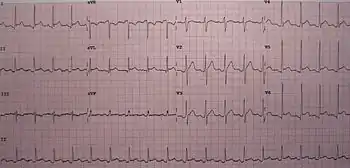

| An ECG showing pericarditis, with ST elevation in multiple leads and slight reciprocal ST depression in aVR. | |

The preferred initial diagnostic testing is the ECG, which may demonstrate a 12-lead electrocardiogram with diffuse, non-specific, concave ("saddle-shaped"), ST-segment elevations in all leads except aVR and V1[11] and PR-segment depression possible in any lead except aVR;[11] sinus tachycardia, and low-voltage QRS complexes can also be seen if there is subsymptomatic levels of pericardial effusion. The PR depression is often seen early in the process as the thin atria are affected more easily than the ventricles by the inflammatory process of the pericardium.